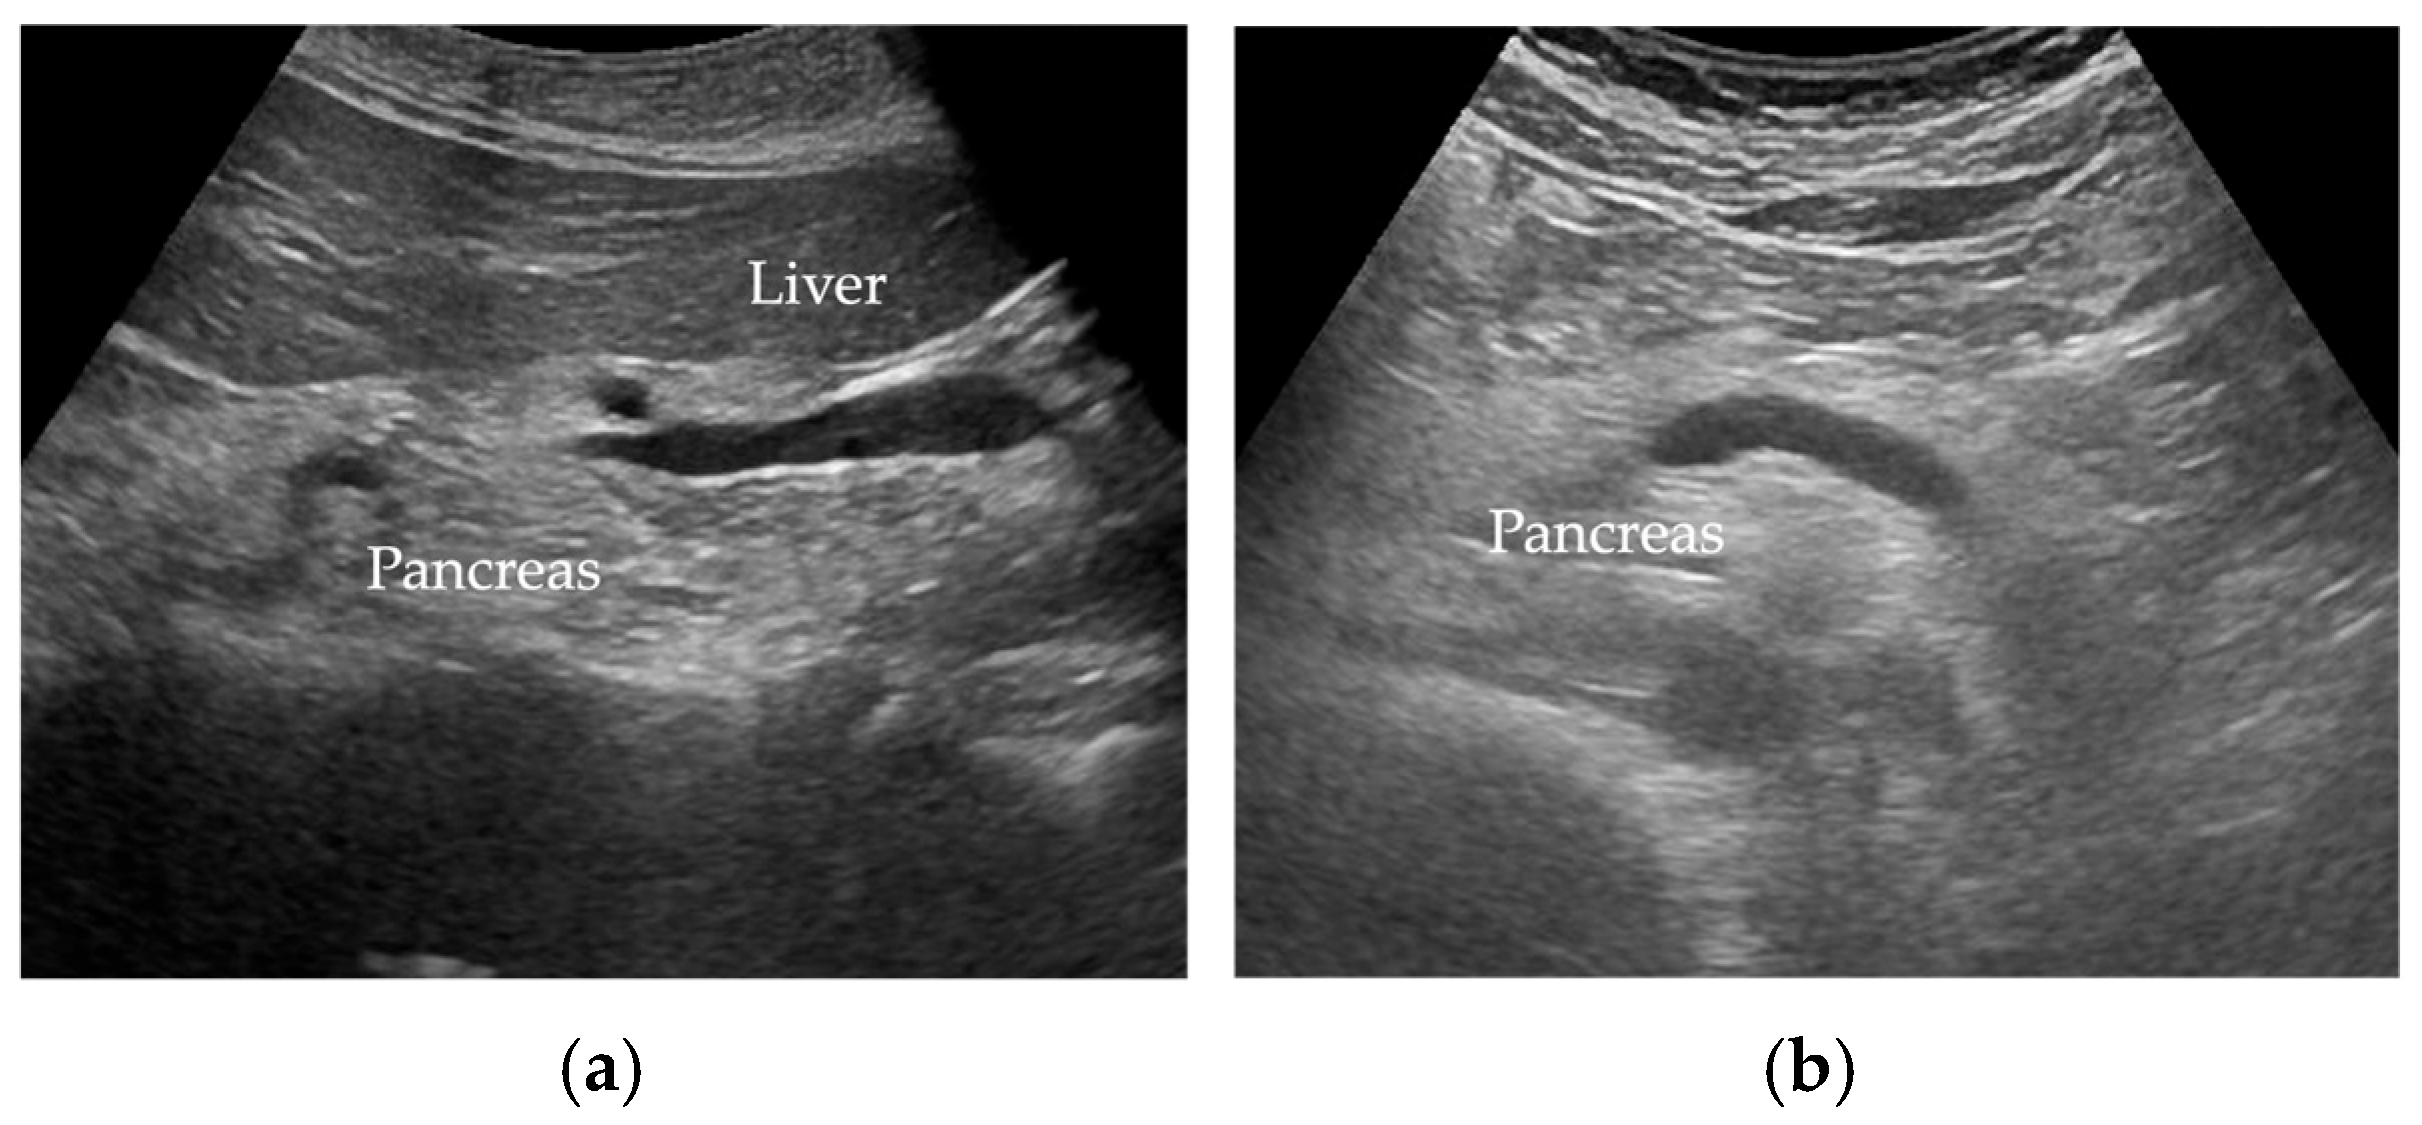

5.1. Transabdominal Ultrasonography (US)